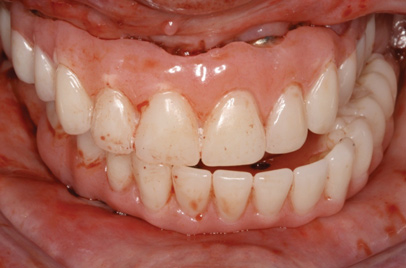

Fig 7. Existing dentition was sound periodontally and reasonably esthetic.

Figure 7

Interceptive implant therapy may then become a consideration earlier in life to create restorations that will not be subject to the latent effect of dental caries as aging continues. An example is shown in Figure 6 and Figure 7; the panoramic film of a 56-year-old man shows several orthognathic and extensive dental procedures historically. All full-coverage restorations had been replaced for a second time, and, again, all evidenced recurrent caries, but the existing dentition was periodontally sound and relatively esthetic.

The choice of removing a caries-challenged but restorable dentition at a younger age is ethically complex. Ultimately, the decision is the patient's alone based on informed consent of all available options. The removal of a potential lifetime of caries activity that is now more predictable than ever may be a viable option for this high-risk segment of a younger patient base.